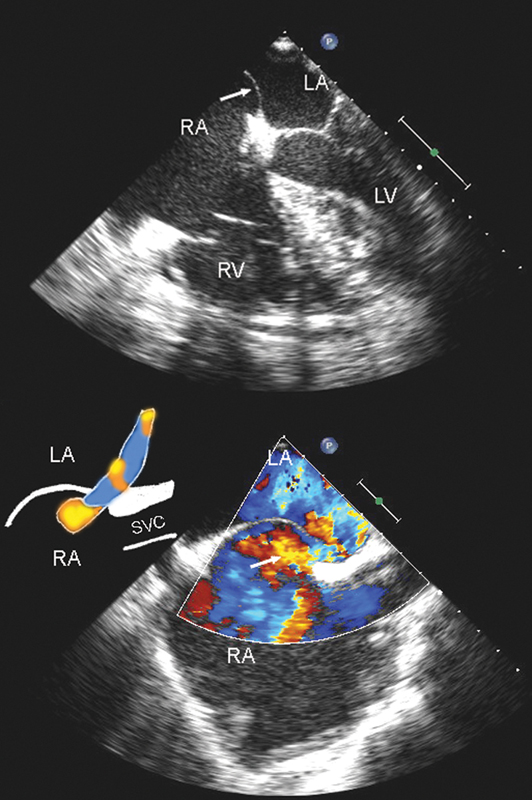

فحوصات تشخيصية لبعض امراض القلب والشرايين التاجية